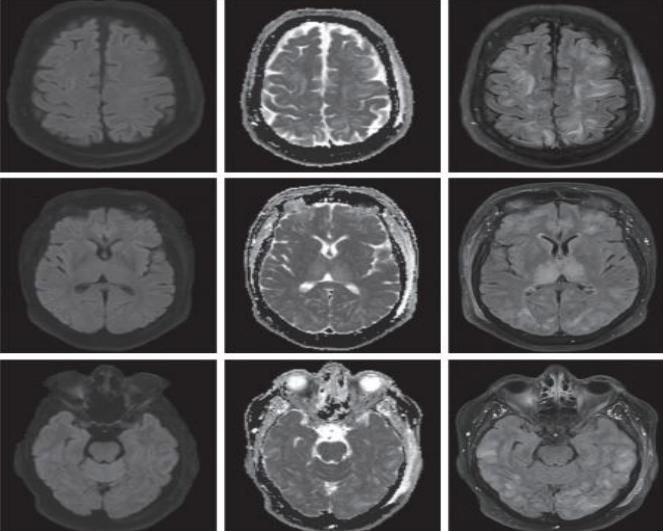

患者女性,26岁,“反复四肢抽搐 11年,言语不利、反应迟钝4天”入院。患者15岁时首次出现癫痫样发作,表现为口吐白沫,头向右侧歪斜,四肢抽搐,伴有意识丧失,持续数秒钟后自行缓解,间隔一段时候后再发,每次发作前多有发热,头痛诱因,诊断为“癫痫”,予德巴金治疗,自行服用半年后停用。患者分别在19岁,21岁,25岁以及今年11月份出现上述癫痫样发作,患者家属诉患者每次癫 痫发作时持续时间均不足1分钟,发作频繁,间歇期逐渐缩短。患者4天前出现言语不利、反应迟钝。

2018.11.3核磁如下:

2018.12.27核磁如下:

2019.1.19核磁如下:

答案:MELAS。其影像典型表现:CT:部分见基底节钙化。MRI:T2WI,FLAIR,DWI序列上相应的高信号;ADC可为高信号,低信号或混杂信号,提示细胞毒性水肿和血管源 性水肿同时存在;磁共振波谱(MRS)提示脑部乳酸的存在。病灶多分布在皮层和皮层下白质,深部皮层不受累;急性到亚急性时期病灶变化可有明显波动,迁移至完全消失;反复发作后脑萎缩。